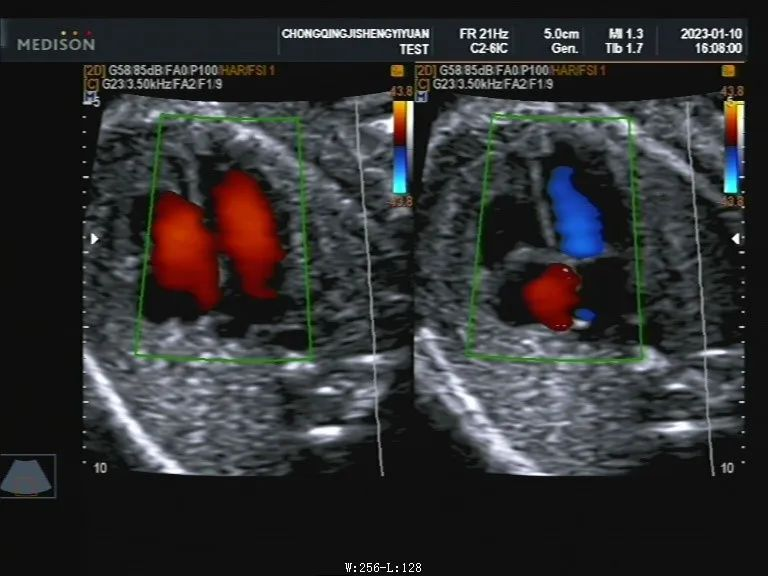

彩色多谱勒超声简称“彩超”,这是一种在清晰度较高的B超声基础上加入彩色多谱勒成像功能的一种技术。彩超能够形成彩色多谱勒超声血流图像,既有黑白超声的优点,同时够提供血流动力学的诊断信息。特别是在心脏、血管方面检查应用广泛。

彩超显示胎儿心脏血流